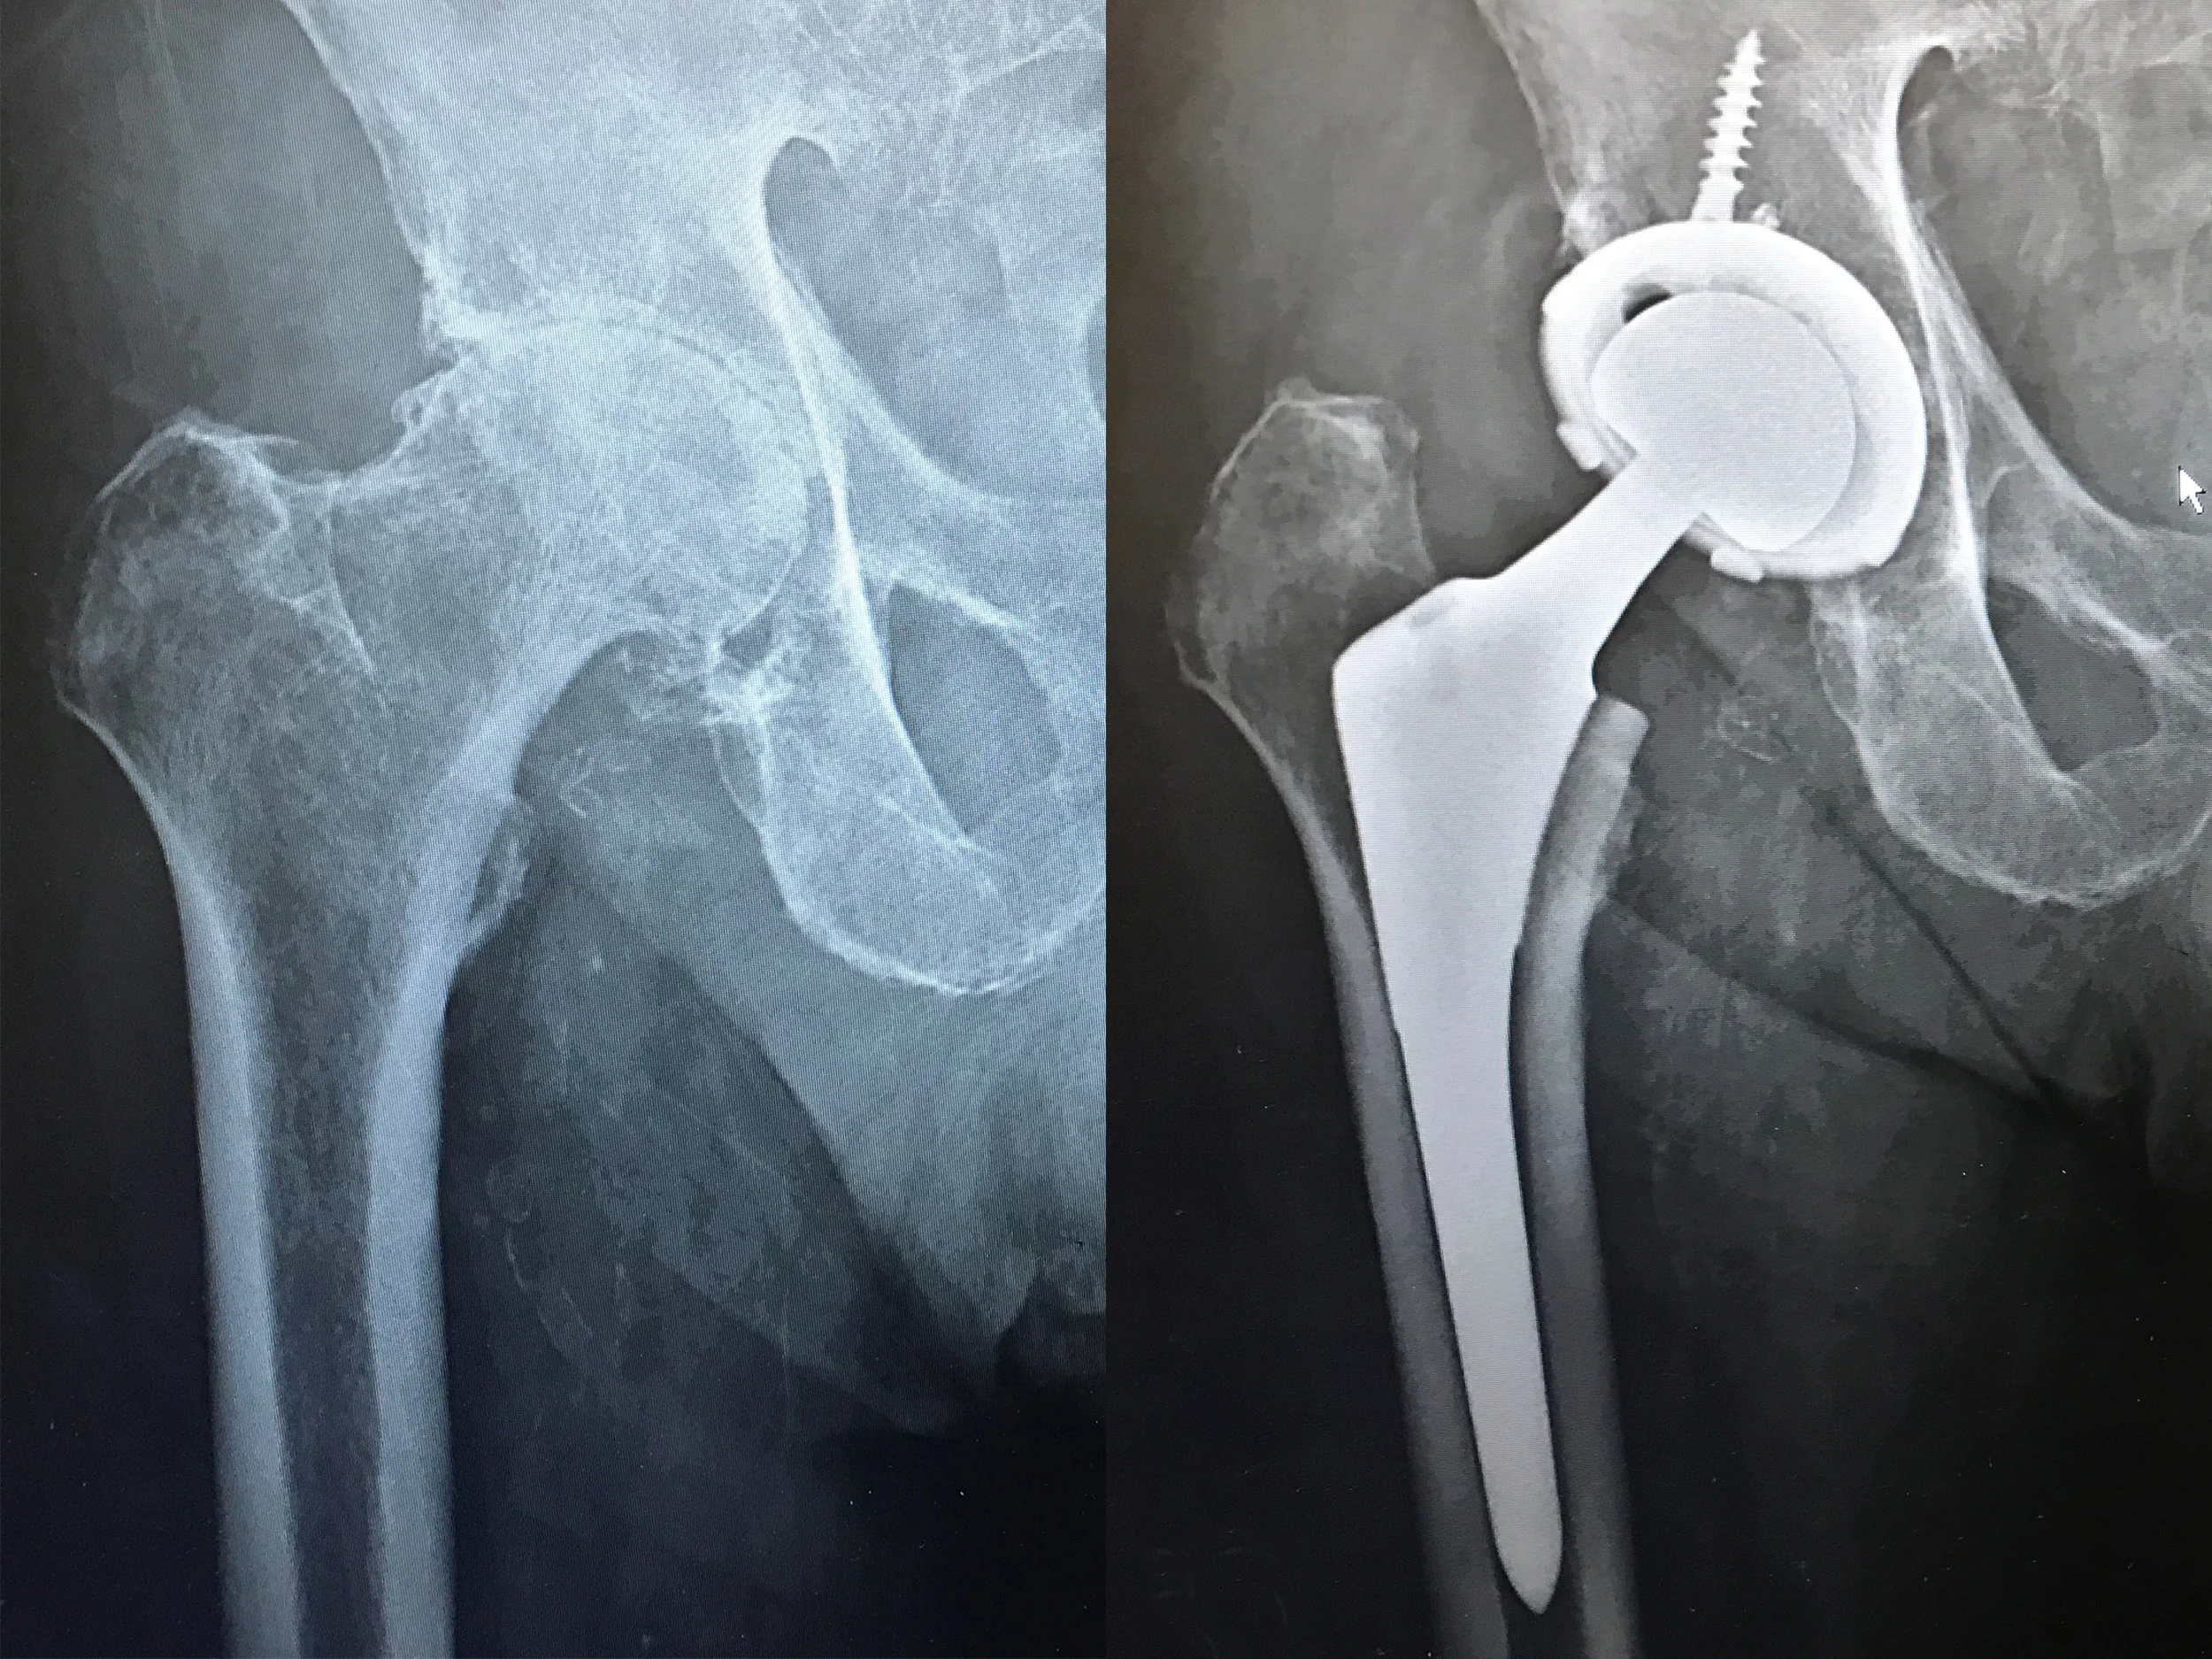

Before and After X-Rays

Before: Bone on bone arthritis with large cysts

After: Total Hip Replacement on 47 y/o female

BIOMET